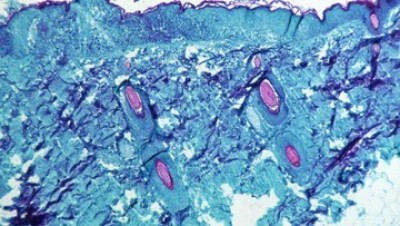

Foto: Penyakit cacar monyet disebabkan oleh oleh virus cacar monyet atau monkeypox virus (MPXV). Begini gejala cacar monyet.( via REUTERS/CDC)

Lancang Kuning -- Penyakit cacar monyet disebabkan oleh oleh virus cacar monyet atau monkeypox virus (MPXV). Ada beberapa gejala cacar monyet yang mungkin muncul.

Ruam terdiri dari lesi yang berkembang dalam urutan berikut:

* Makula, atau lesi berubah warna datar

* Papula atau lesi yang sedikit terangkat

* Vesikel atau benjolan dengan cairan bening

* Pustula atau benjolan dengan cairan kekuningan

* Keropeng